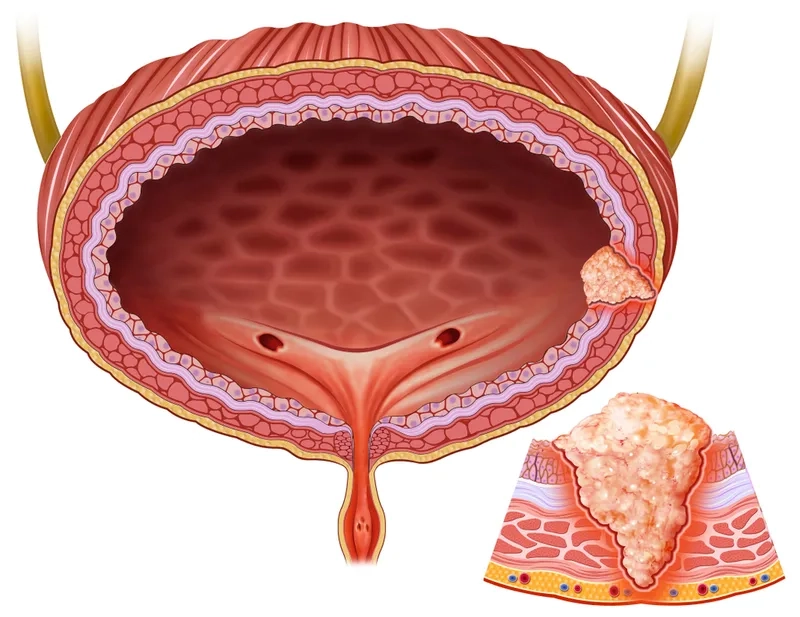

A visual guide to the stages of bladder cancer

Answering the question: what is bladder cancer